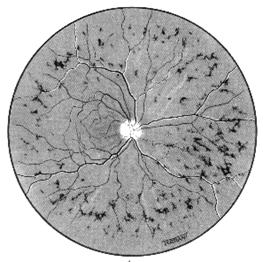

Din punct de vedere oftalmoscopic aspectul este destul de caracteristic, prezenta microanevrismelor cu aspect punctiform, rosii, rotunde si bine delimitate, fiind patognomonica pentru retinopatia diabetica (Fig. 17.6).

Fig. 17.6 - Microanevrisme, hemoragii striate si exsudate dure

in retinopatia diabetica neproliferativa